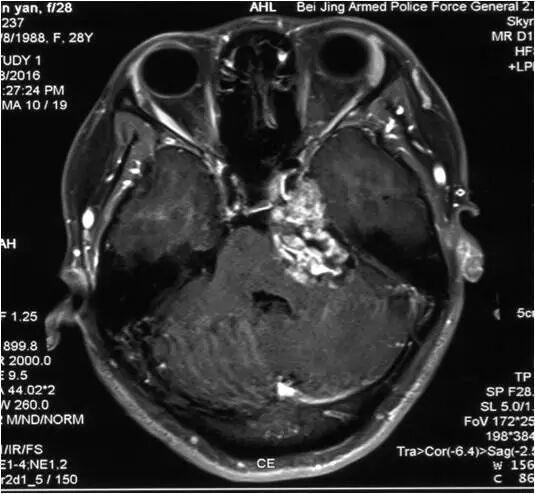

脑桥海绵状血管瘤